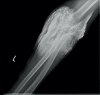

Methods: Two cases were compared in the context of the prevailing literature. One of these was a large volume extravasation of an iodine-based imaging contrast agent with a diffuse distribution pattern, rendering it unsuitable for this method of evacuation. This is contrasted with a case with a more discrete collection better suited to acute evacuation.